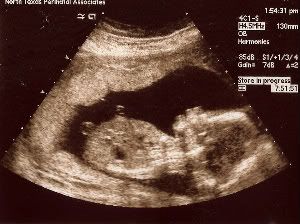

终于等到这一天,不知道是真的那么紧张跟期待,我前一晚竟然失眠了!一直摸着肚子 ,跟宝宝说"宝贝,明天要把脚打开开哦!让爸爸妈妈看看你是小王子还是小公主,那爸爸妈妈就可以正式开始买东西给你了!"

好不容易挨到12.30pm,老公回来接我去做ultrasound,今天的检查,是要看宝宝脑部,心脏等的发育。当然,还有要看宝宝的性别!我们是预约了1点的时间,可是哦,我们竟然等到快2pm才轮到我们!

好不容易盼到医生来了,她先看宝宝的心脏。。看了好几分钟,她突然停止所有动作,指着银幕,神色凝重的样子,当时我看了看老公,眼泪要涌上来了,听着医生说"你看到宝宝心脏有几个白点吗?" 我强忍着泪水点了点头,不知道她要宣布什么坏消息。。。。她继续说"通常这些白点是表示宝宝有可能是唐式儿的征兆之一!可是有很多例子证明 这些白点常常可以在亚洲人/宝宝的心脏看到,可是不代表宝宝会是唐式儿。你的年龄层加上你上次来做的唐式儿检查,报告说你宝宝是唐式儿的机会微乎其微。所以别担心!只是不知道为什么这些白点就是会在亚洲人看到!"

我真的被她吓到了很多下!!

照了心脏,就轮到宝宝的脑,肾脏,脊椎,手脚,眼睛,鼻子,嘴巴。。宝宝动得很厉害!不直是手脚乱挥舞,宝宝是整个身体180度,360度地翻来翻去!连医生都讲"你这个小坏蛋,太好动了吧?"嗨。。有点担心我这个宝贝以后会不会是"过动儿"啊??

等了好久。。医生终于说," 看来我门是看到了B。。O。。。Y。!!!!"

我跟老公虽然没有性别的偏好,可是一听医生这么说,我当场"哈哈哈!"笑出来,因为我可以开始shopping咯!!!!!

然后医生就把银幕停格,让我们"欣赏"宝宝的"小小鸟"!

这一次产检,医生给了我们宝宝的"特写"scan..看到宝宝的头。。我看了又看,跟老公手"我觉得宝宝很象他爸爸哦!!"

宝宝今天19周大了!16.36cm长!